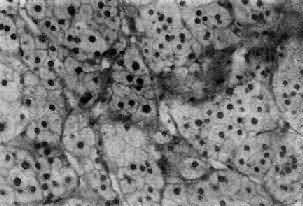

肾上腺皮质(adrenocortical carcinoma)甚少见,一般为功能性,发现时一般比腺大,重量常超过100g,呈浸润性生长,正常肾上腺组织破坏或被淹没,向外侵犯周围脂肪组织甚至该侧肾。小的腺可有包膜。切面棕黄色,常见出血、坏死及囊性变。镜下分化差者异型性高,细胞大小不等,并可见怪形核及多核,核分裂像多见(图15-17)。常转移到腹主动脉淋巴结或血行转移到肺、肝等处。分化高者镜下像腺,如果体小又有包膜,很难与腺区别,有人认为直径超过3cm者,应多考虑为高分化腺

图15-17 肾上腺皮质